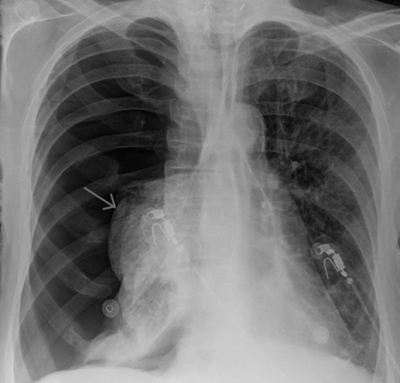

Встречает дежурный фельдшерско акушерского пункта : турист,19 лет,доставлен друзьями,дыхательная недостаточность,давление 80/40,капают. Сделан снимок(смутило отсутствие тени сердца, слева. ну ладно) заключение пневмоторакс справа,ЭКГ не сняли,так как не работает аппарат(верим,реалии нашей медицины,хорошо что хоть рентген есть)не принимал лекарства от бронхиальной астмы 2й день, готов транспортировке! Смотрю на снимок,думаю странный какой пневмоторакс(может напутали что)дежурный уверяет,что рентгенолог опытный и не может ничего путать! Зову рентгенолога,он категоричен,уверяет что я молодой,мало что в жизни видел, а это пневмоторакс!!!Ну раз так,скорее всего спонтанный. Начинаю слушать, верхушечный толчок смещен сильно вправо(сердце слева,соответственно в норме верхушечный толчок тоже слева)в сознании,заторможен,пульс слабый, тахикардия,цианоз(синюшная окраска кожи и слизистой) Дыхание поверхностное,тяжёлое, с участием вспомогательной мускулатуры,т.е. "дышит всем телом".Предположил что все таки это не пневмоторакс,а дыхательная недостаточность в результате бронхоспазма и сердце не на своем месте. В машине сняли ЭГК, все подтвердилось.Борьба с ДН, кислород,Преднизолон, сальбутамол, давление 100/60(приблизительно, так как точных цифр не помню)сатурация 95, привезли в реанимацию.

Астматический статус и декстракардия(сердце расположено справа)все стало на свои места! А "опытный" рентгенолог, теперь работает в одной из частных клиник нашей столицы!

P.S. вот так выглядит декстракардия,фото не мое.